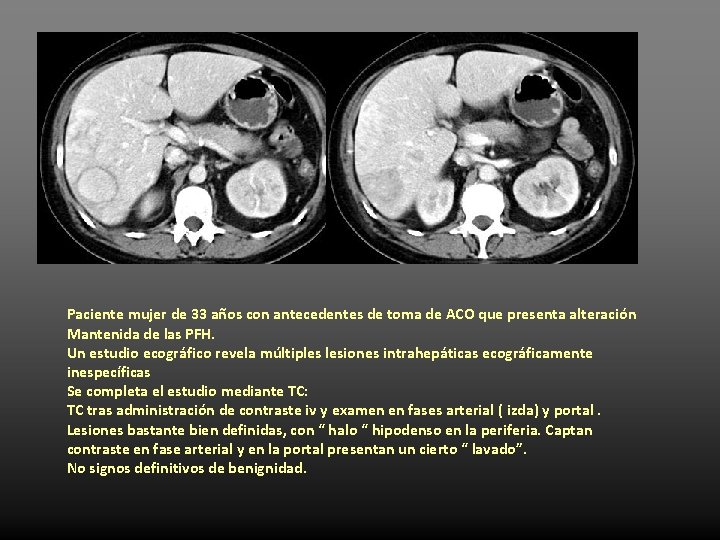

Paciente mujer de 33 años con antecedentes de toma de ACO que presenta alteración Mantenida de las PFH. Un estudio ecográfico revela múltiples lesiones intrahepáticas ecográficamente inespecíficas Se completa el estudio mediante TC: TC tras administración de contraste iv y examen en fases arterial ( izda) y portal. Lesiones bastante bien definidas, con “ halo “ hipodenso en la periferia. Captan contraste en fase arterial y en la portal presentan un cierto “ lavado”. No signos definitivos de benignidad.